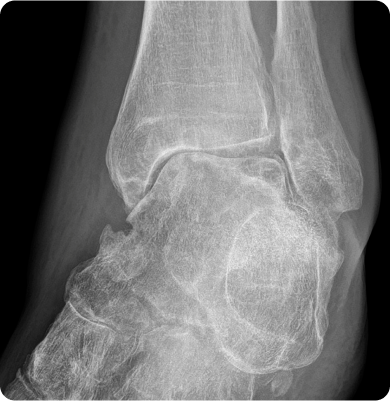

발목을 지지하는 인대가 외부 충격이나 과도한 움직임으로 손상되는 질환

운동 중 발을 접질리는 경우, 울퉁불퉁한 지면에서 걷거나 뛸 때, 하이힐 착용 등으로 인해 발목이 갑자기 비틀리며 인대에 과도한 긴장이 가해지면서 손상됩니다.

발목을 구성하는 뼈와 뼈 사이에 있는 연골이 손상되는 질환

발목에 직접적인 충격이나 비틀림 동작, 과도한 운동량 등이 원인입니다. 특히 스포츠 활동이나 사고로 인한 발목 염좌, 골절 등이 발목 연골 손상을 유발할 수 있습니다.

발목을 구성하는 뼈와 뼈 사이의 연골이 손상되어 염증이 생기고 시간이 지나면서 점차적으로 발목 관절의 기능이 떨어지는 질환

발목에 반복적인 부하가 가해지거나 이전에 발생한 발목 부상, 특히 골절이나 염좌로 인해 관절의 구조가 변형될 때 발생합니다.

관절내시경 수술(인대봉합술, 인대재건술), 인공관절 수술, 발목유합술, 무지외반증 교절술, 연부조직재건술, 근막유리술, 골극제거술, 활막제거술

체외충격파 치료, 도수치료